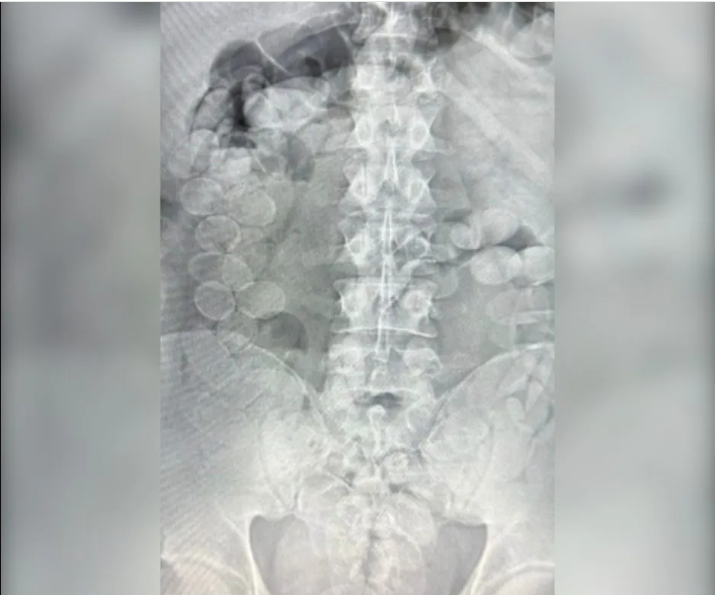

Tras ser trasladados al hospital local, estudios confirmaron la presencia de cápsulas en sus organismos. En total, expulsaron 185 envoltorios con 2,45 kilos de cocaína de alta pureza, cantidad que podría haber generado más de 20 mil dosis.